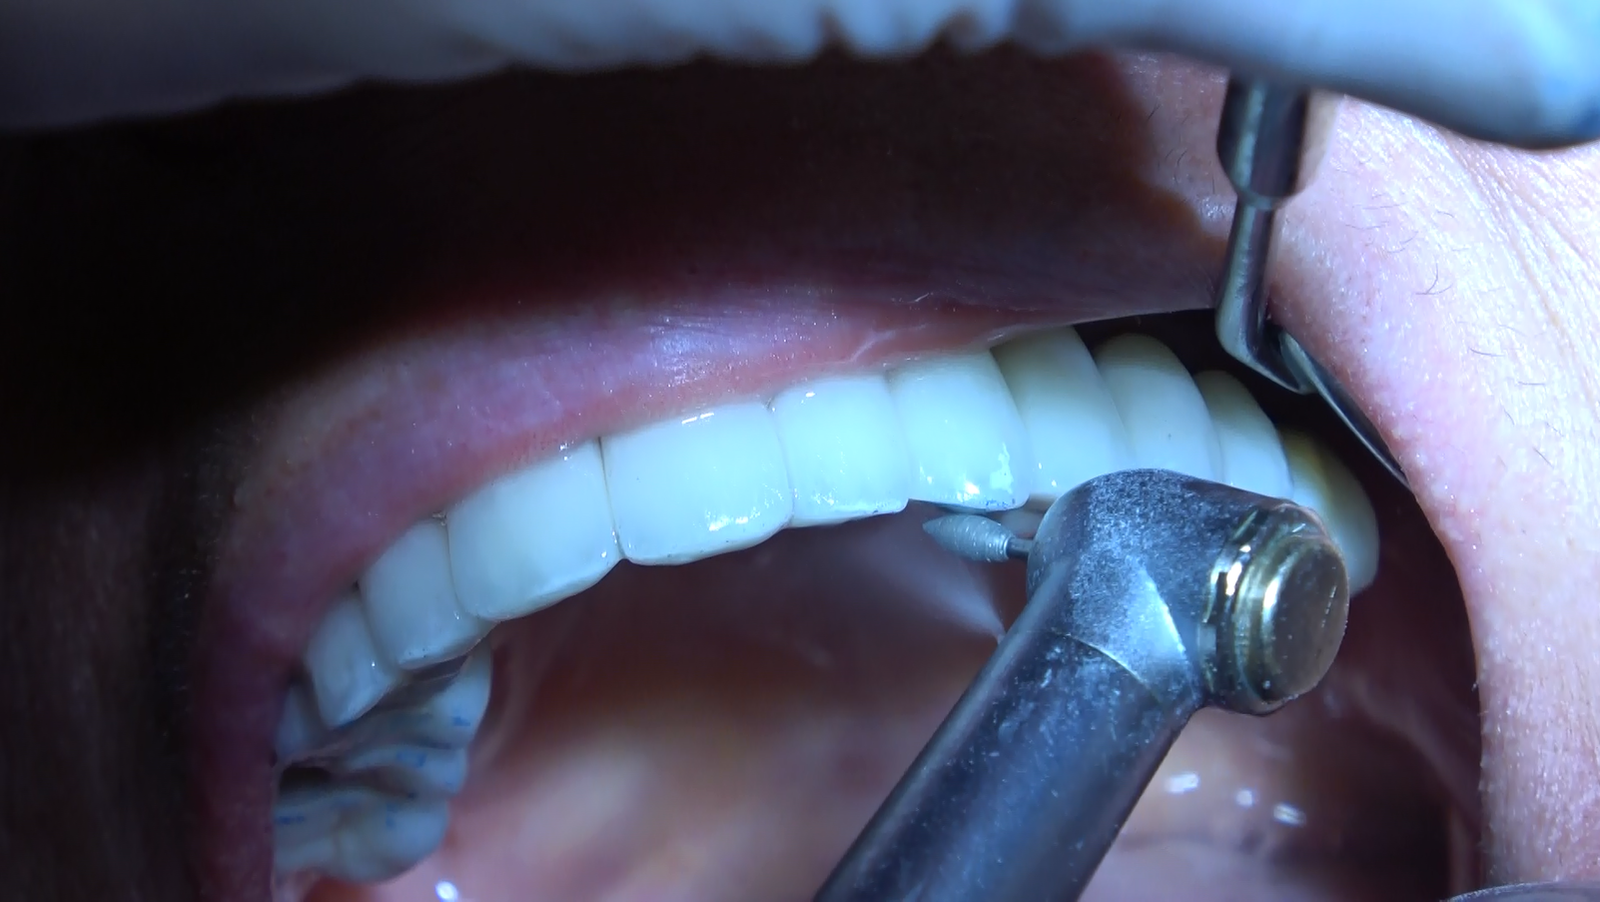

Protesi Circolare: Un Capolavoro Artigianale

Le nostre protesi circolari senza gengiva sono un capolavoro artigianale, realizzato su misura per ogni paziente. La forma circolare della protesi è studiata per adattarsi armoniosamente alla tua bocca, distribuendo uniformemente la pressione masticatoria e garantendo comfort e stabilità.

• Senza Falsa Gengiva:

• La nostra firma è la protesi circolare senza falsa gengiva. Eliminiamo i confini artificiali per un sorriso che sembra naturale e autentico.

• 12/14 Denti su Misura:

• Personalizziamo ogni protesi in base alle tue esigenze, offrendo opzioni con 12 o 14 denti per un sorriso completo e armonioso.

Presso il nostro laboratorio, la realizzazione delle protesi è un’arte. Ogni dettaglio è scolpito a mano, garantendo una precisione e una personalizzazione che vanno al di là delle aspettative. Ogni sorriso è unico, e le nostre protesi sono pensate per riflettere la tua bellezza individuale.

Risultati Naturali che Durano nel Tempo:

Con il nostro approccio olistico, ti offriamo non solo una funzione masticatoria restaurata ma anche un risultato estetico duraturo nel tempo. Siamo consapevoli che il tuo nuovo sorriso sarà parte di te per i prossimi decenni, e lavoriamo affinché ami ogni dettaglio.